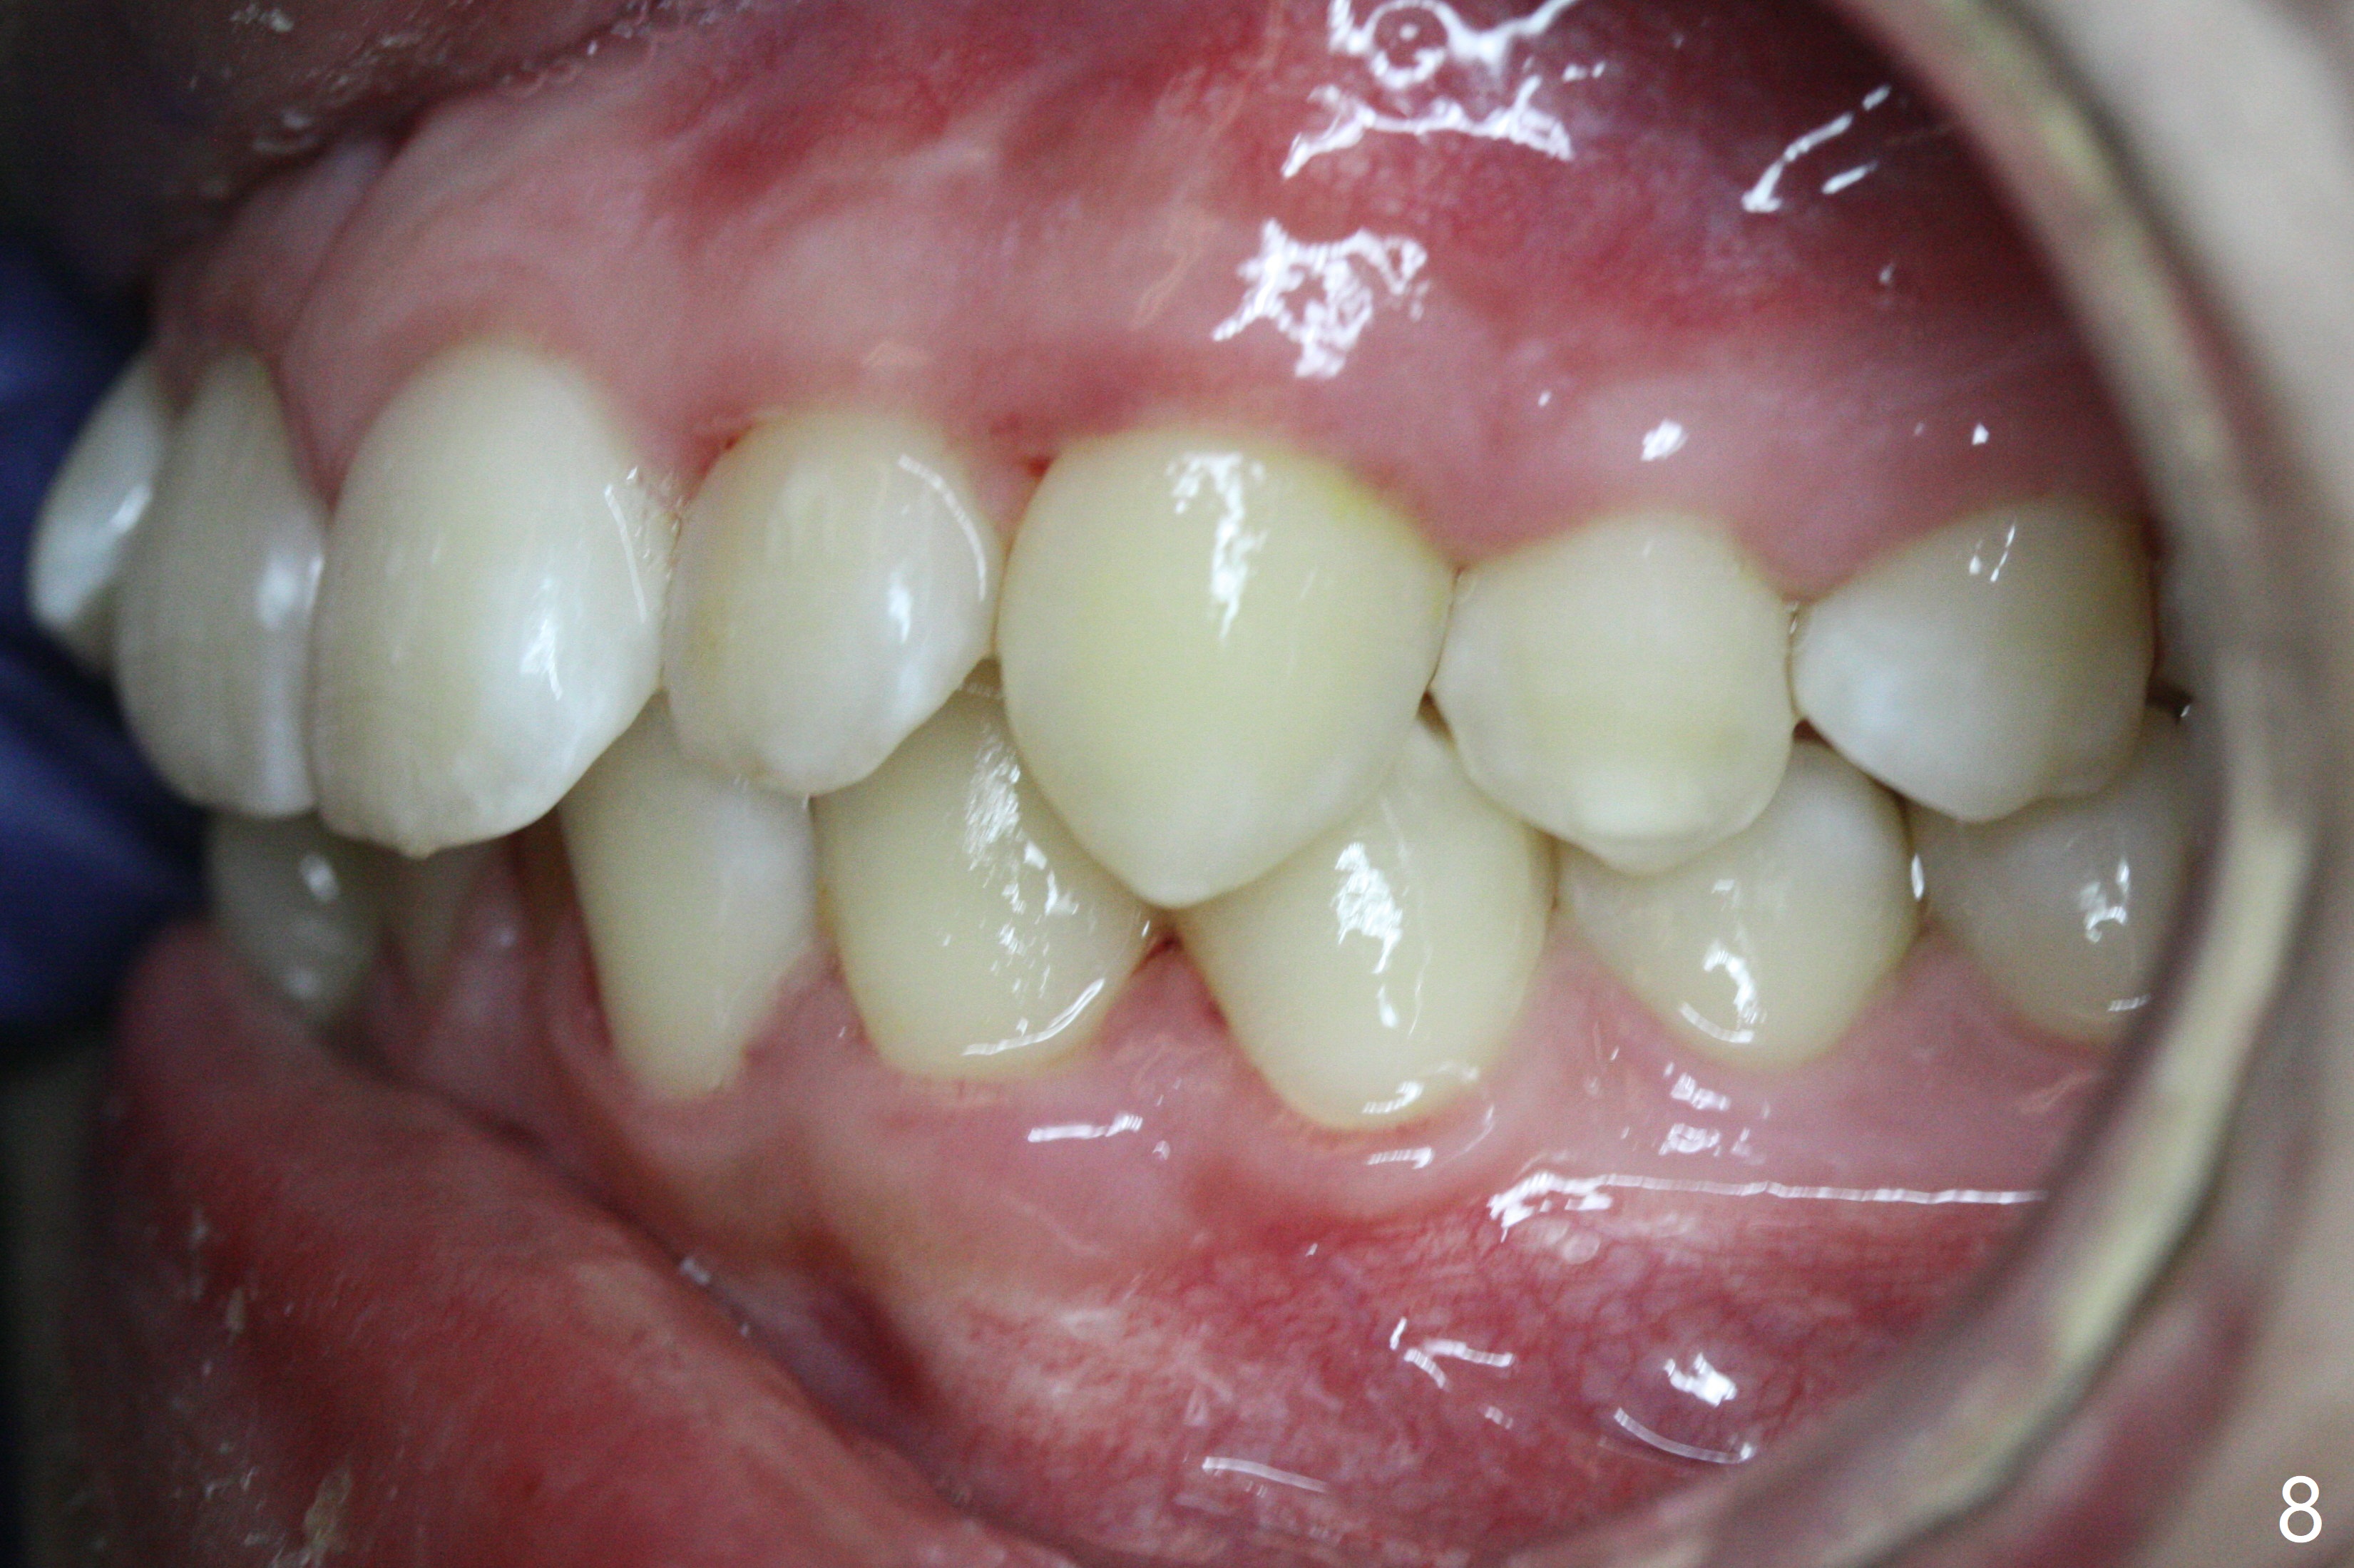

A 15-year-old man requests orthodontic treatment and agrees with extraction.  It appears that the maxilla is more protrusive than the mandible (Fig.1-4, 6,8).  The lower right canine has severe gingival recession (Fig.6,7,10).  Can we extract U4s and LR3 or 2 instead, considering relatively normal alignment in LL (Fig.8, occlusal view)?

Hi Xin, If the patient is protrusive enough (and Class I) to warrant extraction therapy, you will extract one dental unit in each quadrant, normally all four 4s. The wild card in this case is the LR3 recession and the root length being no better than the LR4. So, I would consider extraction of U4s, LL4, and LR3. Bottom line, your LR4 becomes your canine in this case.  Tim Monday, February 5, 2018 9:15 AM